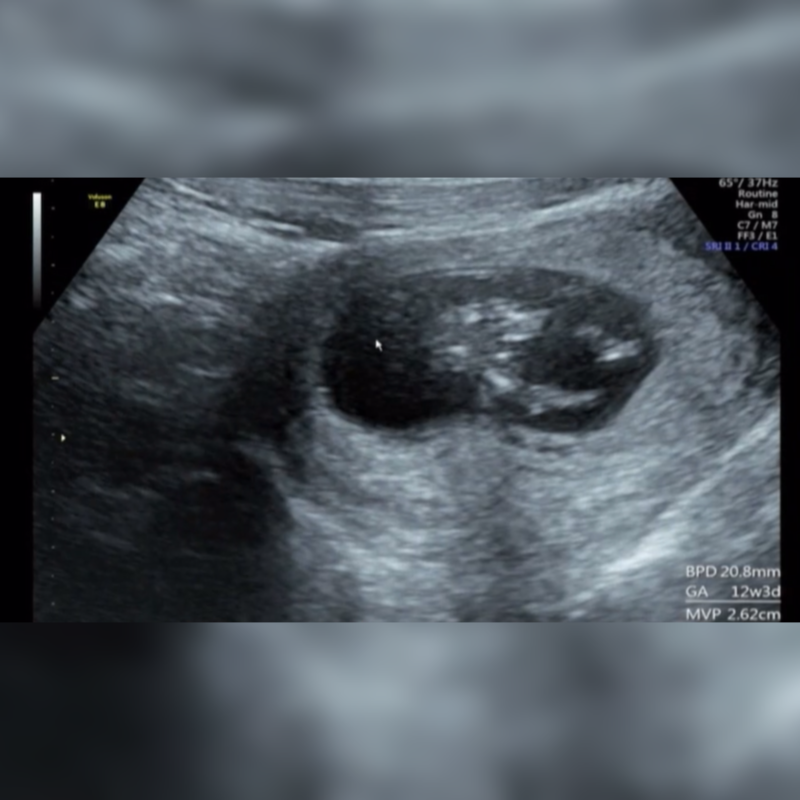

こんにちは! 12w4dのエコーなのですが、お股の間に突起物があるようにみえます。 男の子でしょうか? 女の子でも、このような突起物はありますか?